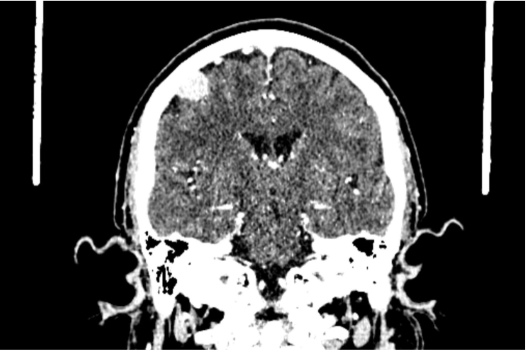

Looking at the axial CT images carefully, you see mass which has taken up the contrast and appears bright. Which of these cerebral cortical regions does this mass overlie?

Prefrontal cortex

Auditory cortex

Primary motor cortex

Visual cortex

According to a colleague of Marina - Lydia - who witnessed the event, the seizure was preceded by abnormal, repetitive movements. Looking again at the coronal view of the CT brain (below) and recalling the motor homunculus, in which body part would these abnormal movements most likely be observed:

Right face

Left face

Right upper limb

Left upper limb

RIght lower limb

Left lower limb

A

The mass is probably closest to the upper limb region of the primary motor cortex. The lower limb is represented more medially and the face is represented more laterally.

Of course, the problem is in the right hemisphere, so this will manifest on the left side peripherally.

Clinically, this phenomenon of abnormal, unprovoked sensorimotor activity is known as a focal or partial seizure, and reflects involvement of distinct funtional areas of cortex.